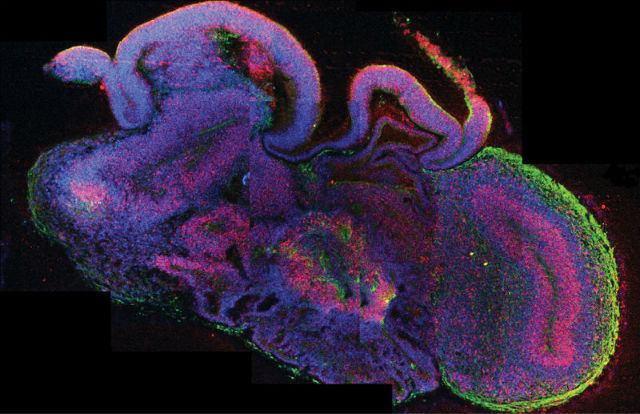

Чтобы вырастить структуры мозга, называемые органоидами, биологи взяли за основу стволовые клетки, способные развиться в клетку любой ткани тела. Их поместили в специальный раствор, способствовавший превращению стволовых клеток в нейроны мозга.

Микроскопические частицы геля, имитировавшего естественные соединительные ткани, обеспечили трёхмерность выращиваемых структур. Нейроны образовались уже на 8-10 день после начала эксперимента, а на 20-30 день учёные заметили, что клетки выросли до 3-4 миллиметров в диаметре. Таким образом они получили нейроны различных отделов — коры или заднего мозга, к примеру.

Более того, выращенные таким образом клетки мозга способны самоорганизовываться подобно тому, как это происходит в естественной среде при развитии эмбриона.

Рассмотрев полученную структуру под микроскопом, нейробиологи заметили, что отдельные её части взаимодействуют друг с другом.